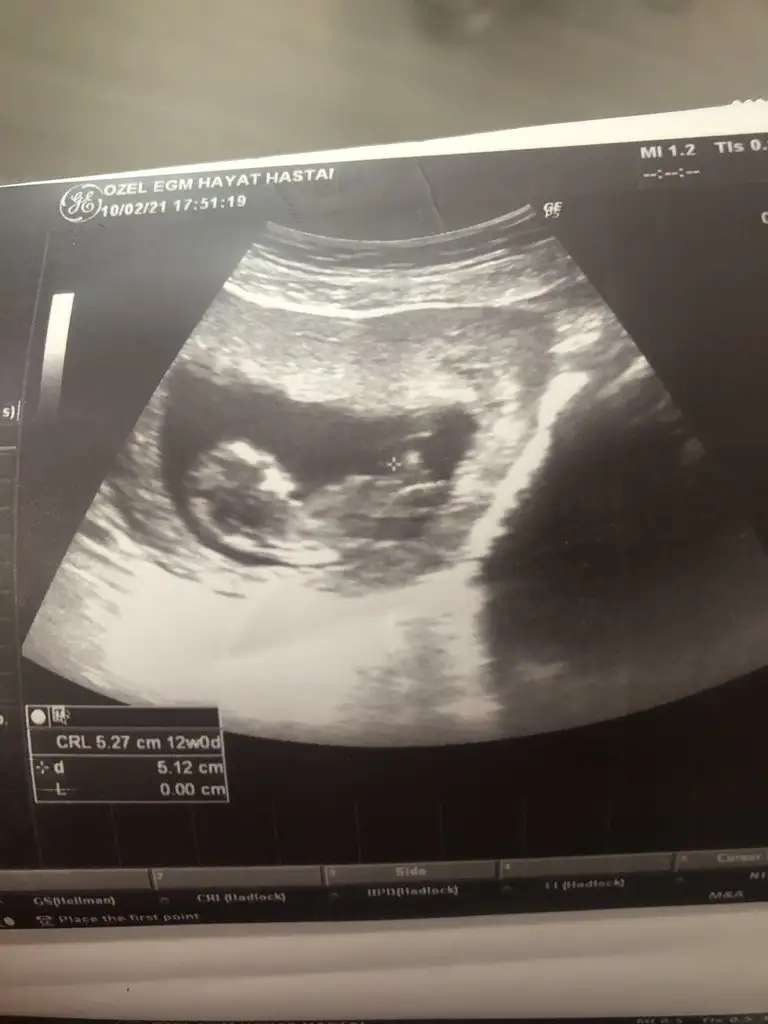

• IMG-20210206-WA0007.webp

IMG-20210206-WA0007.webp

19,1 KB · Görüntüleme: 69